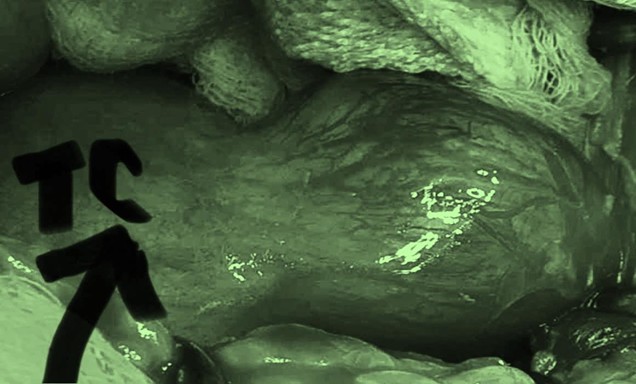

⏰ Vào lúc 13 giờ 45 phút ngày 17/12/2025, ê-kíp phẫu thuật Khoa Phụ sản đã tiến hành phẫu thuật mở bụng. Trong quá trình phẫu thuật, các bác sĩ đã thoát khoảng 3 lít dịch nang màu trắng trong, đồng thời cột và cắt phần phụ phải. Ca phẫu thuật diễn ra thuận lợi và kết thúc lúc 14 giờ 15 phút cùng ngày.